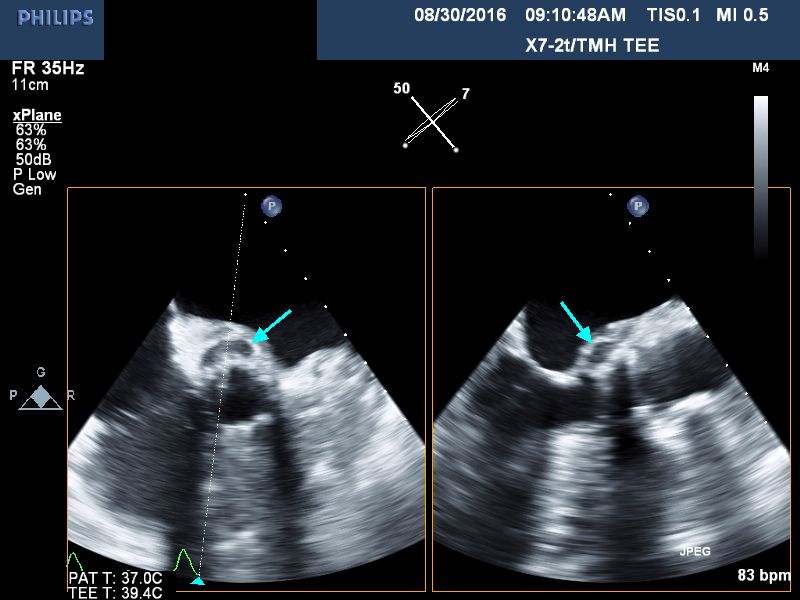

Case Presentation: 85 year old female was admitted on account of lethargy and decreased oral intake for the previous week, and evidence of anemia. She had undergone a transcatheter aortic valve replacement(TAVR) 5 months prior for her management of her severe aortic valve stenosis. Additionally, she suffered from recurrent gastrointestinal bleeding due to arteriovenous malformations, thought to be related to her valvular disease.(Heyde syndrome).Upon presentation she was febrile; temperature of 100.6 F, Heart rate was 87/min, Blood pressure: 121/56mmHg. She was not hypoxic. She was ill-appearing with a mild degree of pallor but anicteric. She had normal heart sounds with a 2/6 systolic murmur at her right upper sternal border. Chest: No wheezes or crackles. Abdomen: Soft and non-tender. Stools: heme-negative. CNS: Awake and alert. No motor deficits. EXT: no edema, clubbing, nodes or hemorrhages noted. Lab. data: WBC :18.1, Hb: 8 g/dL, AST 133 iu/L, ALT 80 iu/L, direct bilirubin 0.6 mg/dL, lactate 1.3 meq/L .Blood cultures were obtained and she was started on broad spectrum antibiotics. Her initial set of blood cultures returned positive for Enterococcus faecalis and she was placed on IV Vancomycin. Transthoracic echocardiogram revealed a well seated bioprosthetic aortic valve with a gradient of 31 mmHg but without any evidence of vegetations. Subsequent transesophageal echocardiogram demonstrated a 5 mm by 8 mm mobile density attached to the ventricular surface of the bioprosthetic aortic valve leaflet (Fig. 1) as well as a 6 mm by 16 mm echolucent space in the aortic root (Fig. 2), consistent with aortic root abscess.